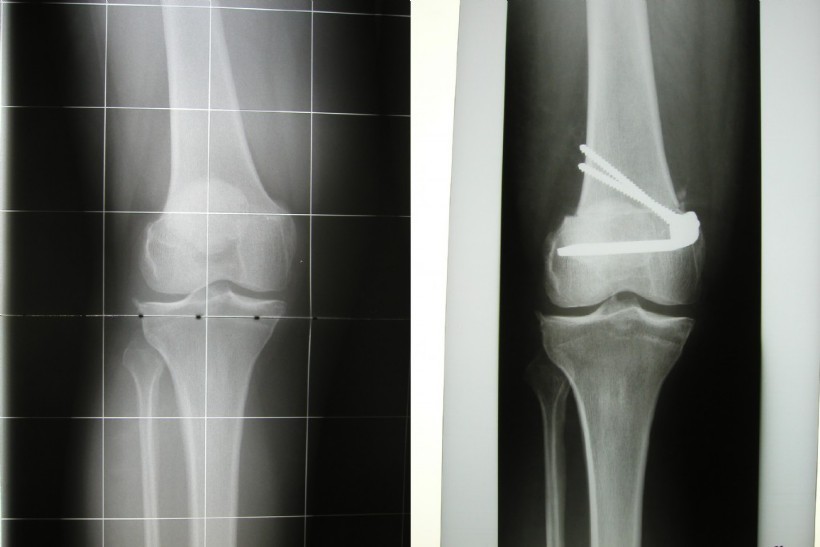

An X-leg is corrected due to mechanical reasons at the thigh. The principle is the same.

Left: X-leg

Right: After the adjustment a normal leg axis.